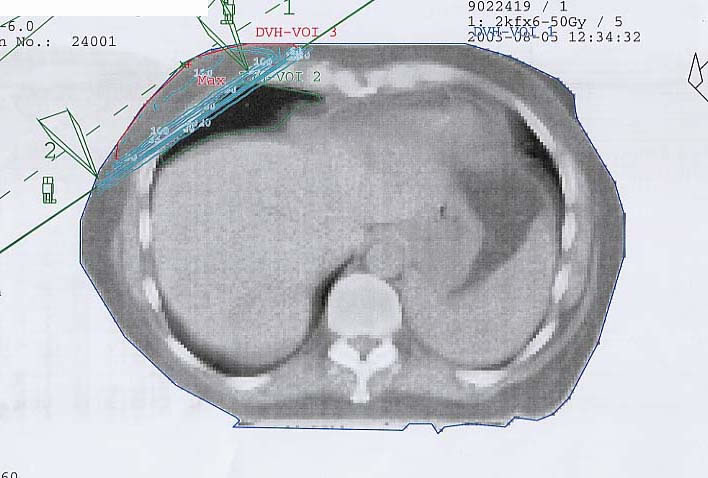

Mammakarzinom: Bestrahlungsplan

Einführung aktuelle Bilder - Einführung Bestrahlungspläne - Einführung Demonstration